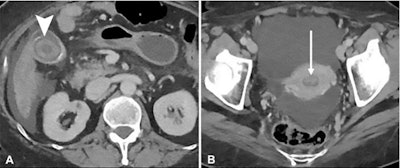

The study included 10,090 body CT scans read by 32 fellows during off hours between June 2014 and June 2018. The researchers classified discrepancies that affected follow-up clinical care as errors, comparing the error rate for daytime readings (7 a.m. to 5:59 p.m.) and nighttime readings (6 p.m. and 6:59 a.m.). They also compared error rates in the first and second halves of the shift.

Overall, the team found a 2% error rate for daytime interpretations and a 3% error rate for night reads, with 69% of readers having higher night interpretation error rates. The group also found that there were more errors in the second half of the night shift compared with the first half.